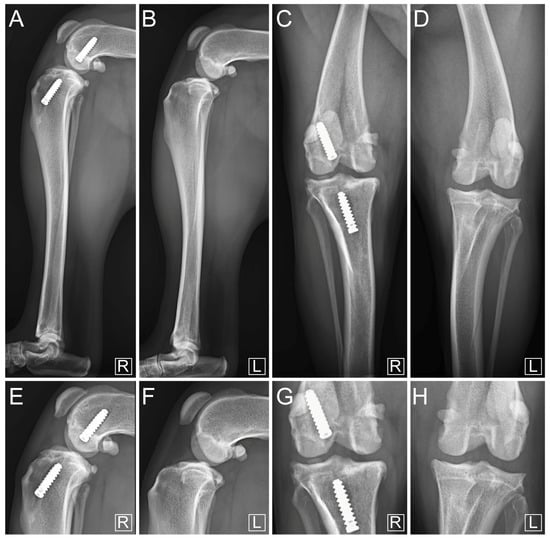

2.5. Immediate Postoperative Evaluation

3. Results